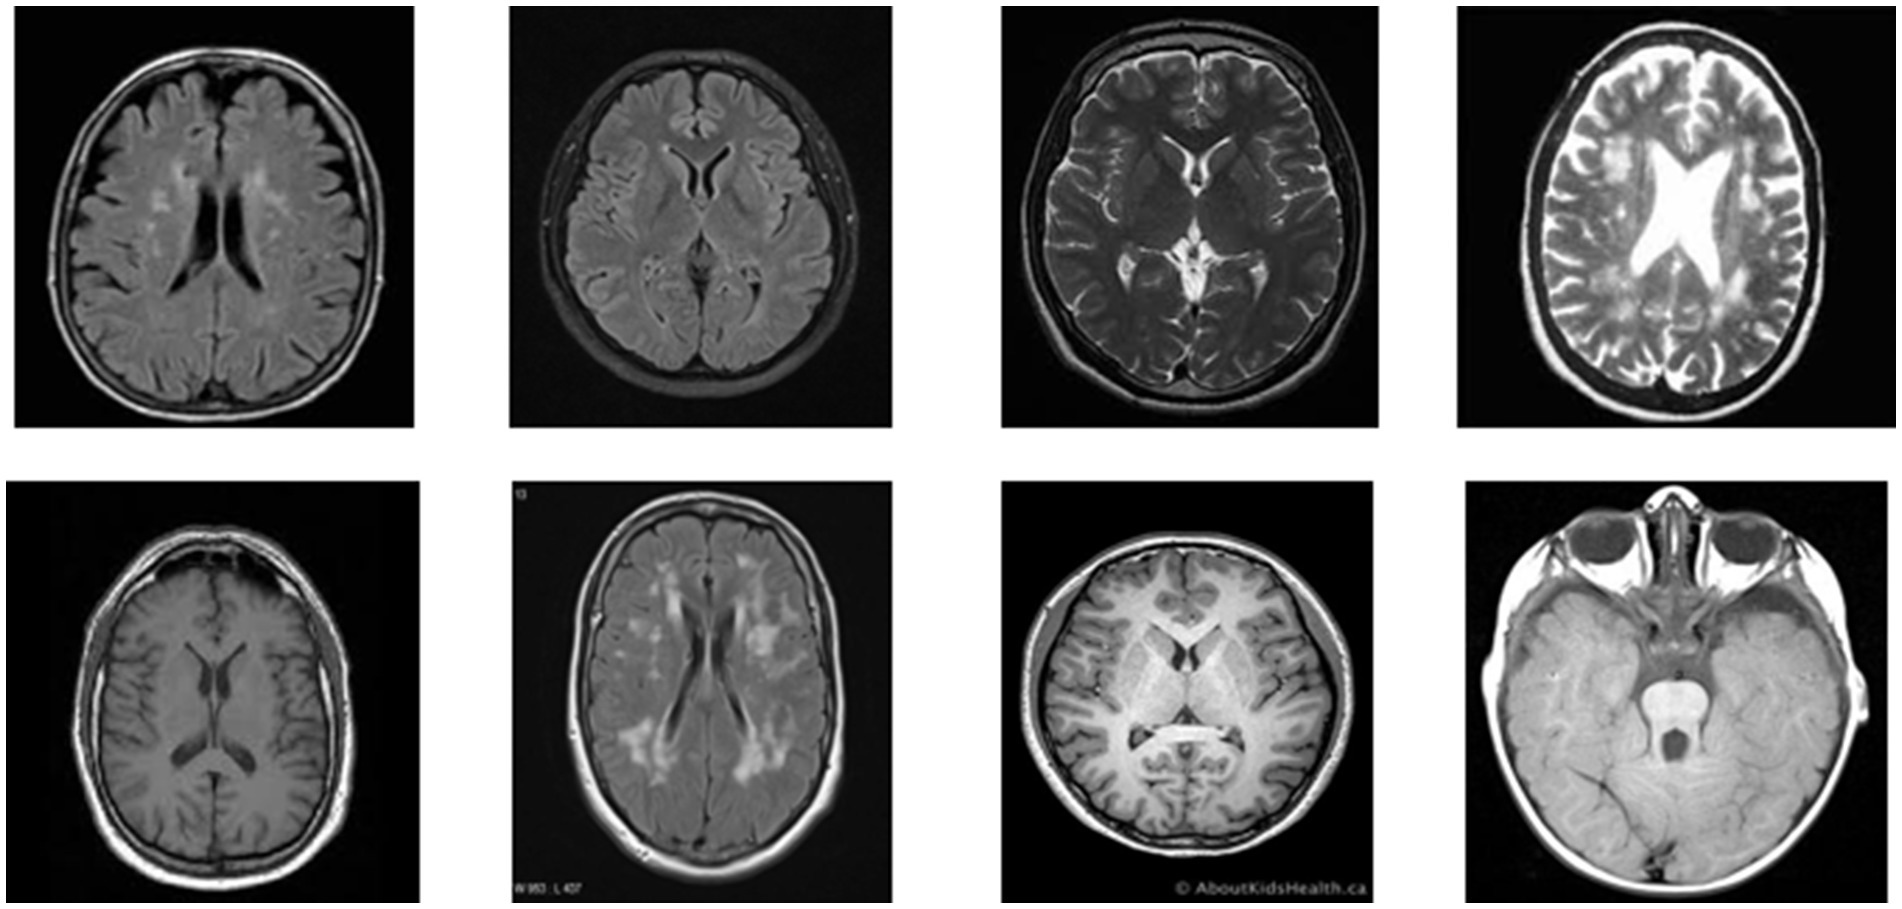

Figure 1 presents a representative MRI scan of a healthy brain, illustrating normal anatomical structures without any abnormal growths. In contrast, Figure 2 visualizes an MRI scan with a visible brain tumor, showing abnormal intensity regions that are indicative of pathological tissues. Figure 3 illustrates the distribution of MRI images across the defined classes, revealing an inherent imbalance in the dataset, which was addressed using augmentation techniques and loss function adjustments to ensure model robustness and generalizability.

Figure 1

Visualization of healthy MRI scan.